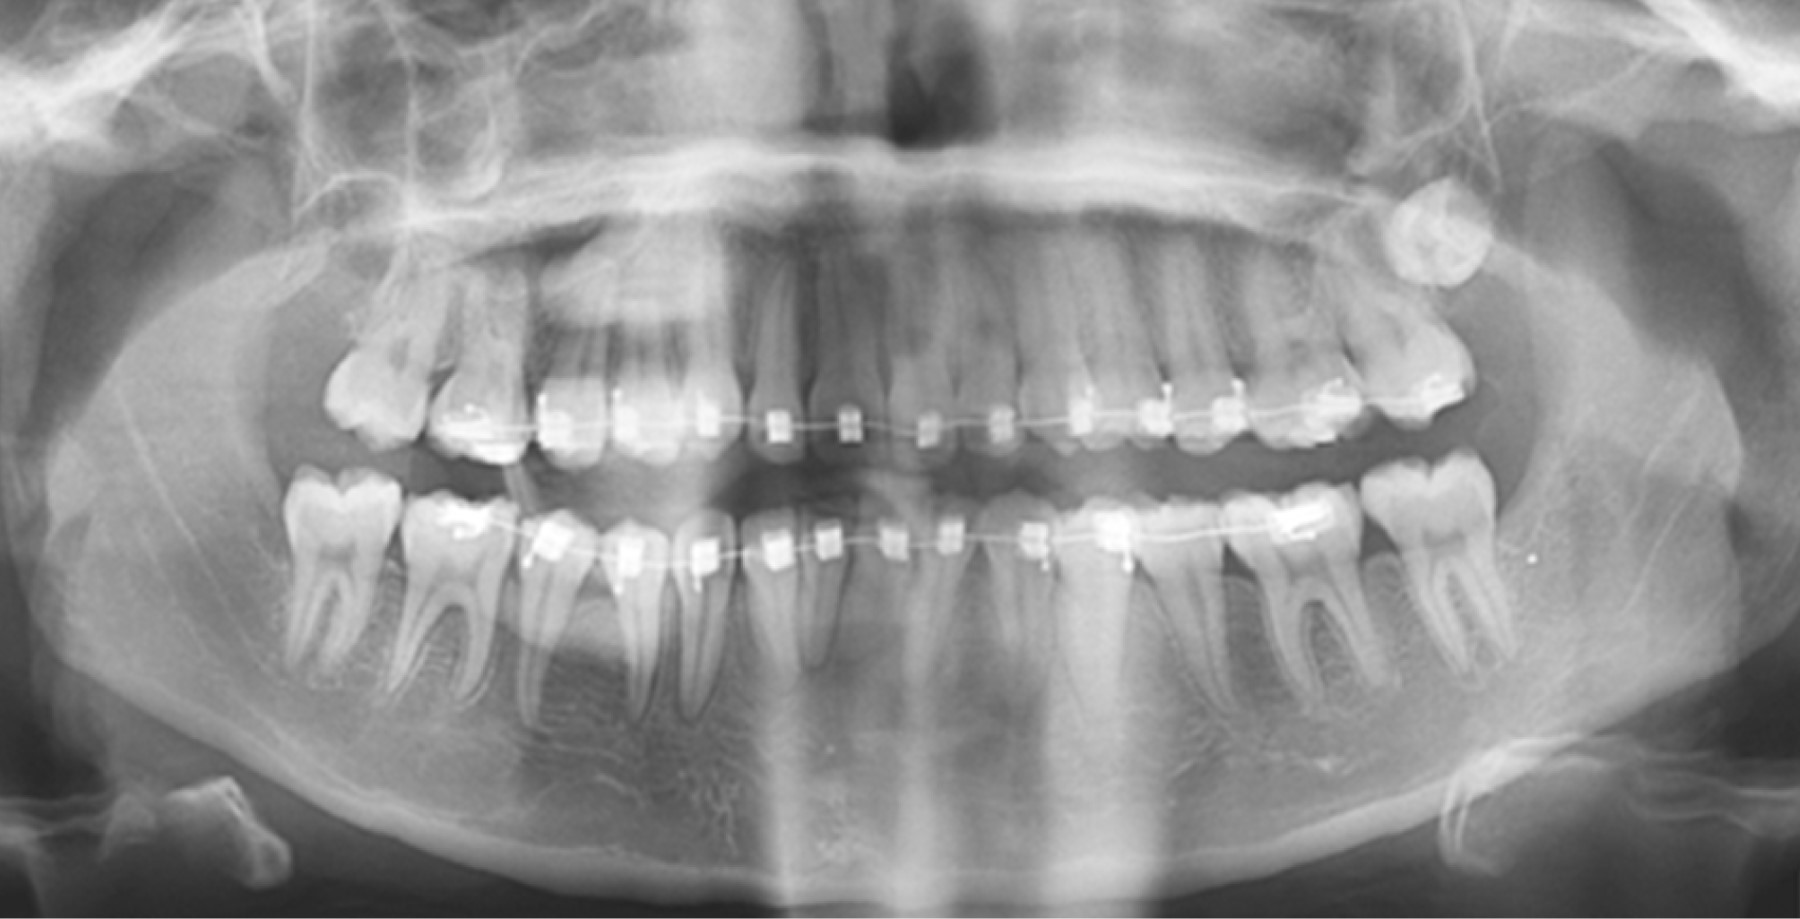

Se trata de un paciente femenino de 16 años de edad, natural y procedente de Caracas, Venezuela, sin antecedentes médicos conocidos, quien acude al Servicio de Cirugía Oral del Hospital Ortopédico Infantil para la valoración y extracción de terceros molares, los cuales clínicamente no se encontraban presentes en boca. Al examen radiográfico se observaron las unidades dentarias (UD) 18 y 28 retenidas en posición vertical según Winter a la altura de la porción apical de la raíz de la UD 17 y 27, respectivamente (Figura 1). Durante la extracción de la UD 28, dicha unidad es perdida de vista por parte del operador, por lo que solicita radiografía panorámica para su ubicación (Figura 2). Se indica antibiótico, analgésico y antiinflamatorio, así como medidas antiedema. Posteriormente, se solicita tomografía de haz helicoidal para su planificación quirúrgica.

En la evaluación radiográfica postoperatoria, usando una radiografía panorámica se observa la UD 28 en el espacio correspondiente a la fosa pterigomaxilar en una posición transversal según Winter, motivo por el cual se decide realizar una tomografía de haz helicoidal.

Figura 2